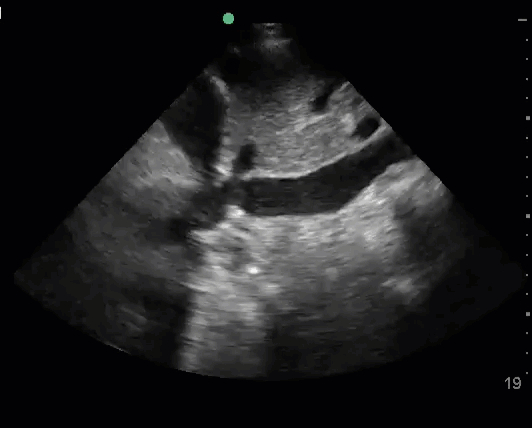

Case reports have described both pericardial effusion and cardiac tamponade as complications of myopericarditis in COVID-19.13,14

Point of care echocardiography has both high sensitivity and specificity for diagnosing pericardial effusion. The subxiphoid view is the easiest window for detecting pericardial effusion, as the most dependent portion of the pericardium is closest to the probe. In this view, pericardial fluid should be seen along the right heart border. In the parasternal long axis view, the most dependent portion of the heart is deep to the left ventricle, so pericardial fluid should be seen along the LV free wall. The pericardium is bound by the descending aorta, so pericardial fluid will track between the descending aorta and the LV, while pleural fluid will track posterior and lateral to the descending aorta.

In the setting of a large pericardial effusion and hypotension, assume the patient is in cardiac tamponade. If the patient is hemodynamically stable, it can be helpful to assess for echocardiographic signs of tamponade to anticipate the potential for decompensation.

Identifying a new pericardial effusion in the setting of COVID-19 suggests either pericarditis or myopericarditis. Use ultrasound guidance to treat cardiac tamponade with pericardiocentesis.